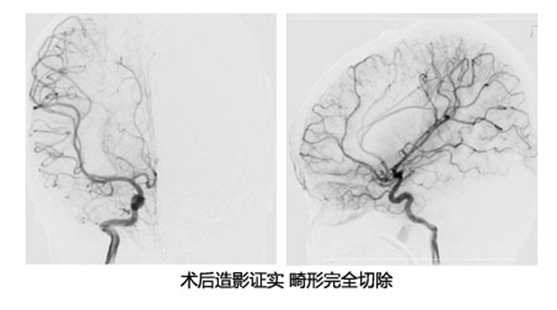

病例1 额叶动静脉畸形

患者曹某,男,3岁,因“突发头痛、呕吐3小时”于2016-02-20入院;专科检查: 昏迷,不能睁眼,不能发音,刺痛躲避。双侧瞳孔等大等圆,直径2.0mm,对光反射灵敏;辅助检查:头颅CT提示:右额叶脑出血并破入脑室、脑积水、脑肿胀。入院后完善CTA检查,急诊手术治疗。术程顺利,术后患者恢复良好。